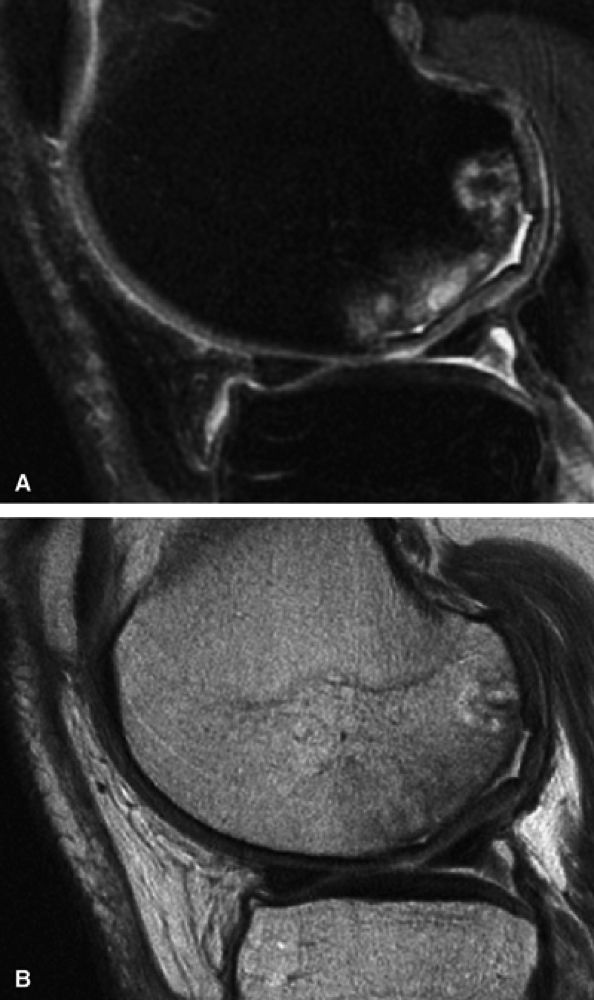

Heavily T2-weighted sequences, with echo times in excess of 80 msec, depict the cartilage as being relatively hypointense compared to high-signal-intensity fluid. It is important to remember, however, that because of the normal stratification of the extracellular matrix in cartilage, T2 values are shorter in the radial zone (closer to the subchondral plate) than in the transitional zone, where the collagen is more randomly oriented and T2 values are prolonged. This normal stratification can be perceived on appropriate cartilage-sensitive scans and provides insight into the cartilage ultrastructure (Fig. 7.3).

With longer echo times there is poor delineation between the basilar components of the cartilage and the subchondral plate. This may account for factitious thickening of the subchondral plate and thinning of the cartilage (see Fig. 7.3).

FIGURE 7.3 ● (A) Sagittal fast spin-echo MR image of the knee in a 39-year-old man performed on a high-field system (1.5 Tesla) demonstrates poor distinction between the subchondral plate and adjacent basilar components of cartilage at a TE of 110 msec (white arrow). (B) Corresponding image with all acquisition parameters held the same except for a moderate TE of 27.5 msec demonstrates improved cartilage–subchondral bone distinction (black arrow).